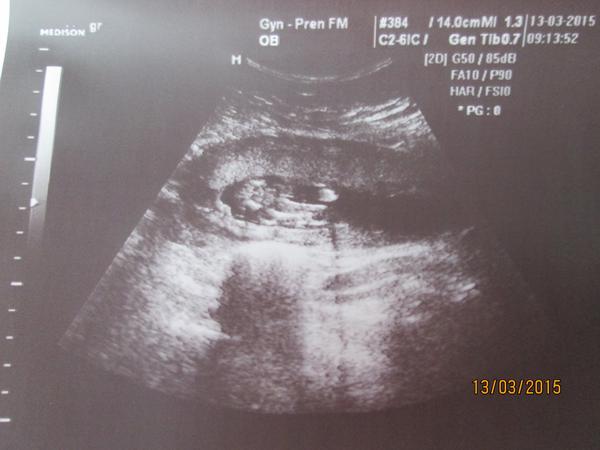

ty fotky co jsem sem dala jsou ze 13tt a to pohlaví vypadá tedy jako jsi sem @ronyx dala ..

A to je fakt nerozpoznatelný i když tady holky tipuji co vidí na mem snímku...... tak to mají muj obdiv

Ahoj holky.Dnes kontrola u dr. jsem 16 tt.Vyfotila mi rozkrok,ale já se v tom nevyzdám.Nevím ani kde jsou nohy natož kde má být údajně pohlaví.Je tu nějaký odborník který to pozná? 🙂 Dr. mě napíná a prý nechá na jiném dr. ať mi řekne co to bude.Kontrola ale až za měsíc 😒

@jarmulka Nevyznáš se v tom prosím ty? 😒 Obě fotky jsou stejné,jen ta druhá je zvětšenina

A můžete mi prosím holky některá z vás nějak zakroužkovat,kde mám hledat?Já fakt ani nemám ponětí 😀

Holky,kde tam vidite pindoura s kulkama?ja se tady snazim stahnout aplikaci do telefonu,abych mohla fotku oznacit a furt nemuzu nic najit ☹ chtela bych oznacit to kavove zrno,ktere vidim 😀

@anetka1701 no tak tam presne vidim kavove zrno 😀

@emily2015 kávová zrna jsem viděla zatím naživo dvě a nějak to vypadalo prostě jinak než tohle... :oD

@anetka1701 ja jsem zase videla na utz pytlik s kulkama a take to vypada naprosto jinak 😀